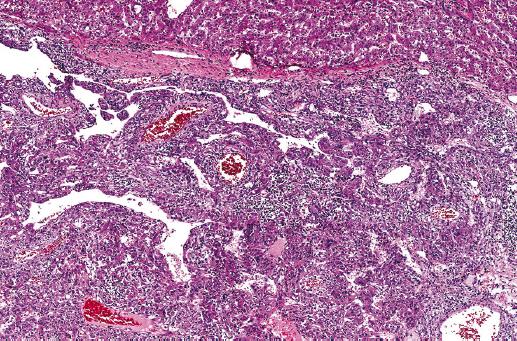

La enferma recibió el alta al quinto día postoperatorio sin ninguna complicación. El resultado de la anatomía patológica mostró la existencia de un PEComa (angiomiolipoma epitelioide monotípico) mayor de 10 cm, con presencia de extensas áreas de necrosis en su interior y ausencia de permeación vascular. En el plano microscópico, la neoplasia se encontraba separada del hígado por una seudocápsula fibrosa, y estaba constituida por células epitelioides, poligonales, algunas veces fusiformes, y dispuestas de forma perivascular. Dichas células presentaban abundante citoplasma eosinófilo, claro de modo ocasional, con núcleos vesiculares grandes y atípicos, y nucléolo predominante (Figs. 2 y 3), signos típicos de este tipo de tumores. Se realizó inmunohistoquímica, también consistente con PEComa: positivo para vimentina, AML, HMB45 (Fig. 4) y Melan-A (Fig. 5), y negativo para proteína S100 y desmina. Se determinó a su vez el índice proliferativo mediante Ki67, que fue del 10%.